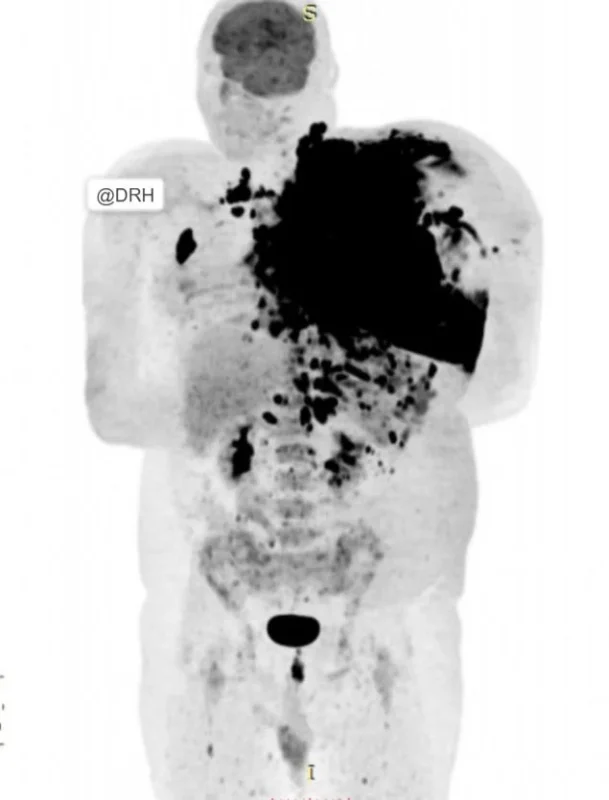

Presenting a case of ‘Anaplastic lymphoma’ which shows the importance of FDG PET/CT in treatment response assessment.

The patient initially presented with:

- Extensive lymphadenopathy involving both sides of the diaphragm

- Predominant disease burden in the left upper hemibody.

- Associated pleural effusion and nodular involvement: Image A